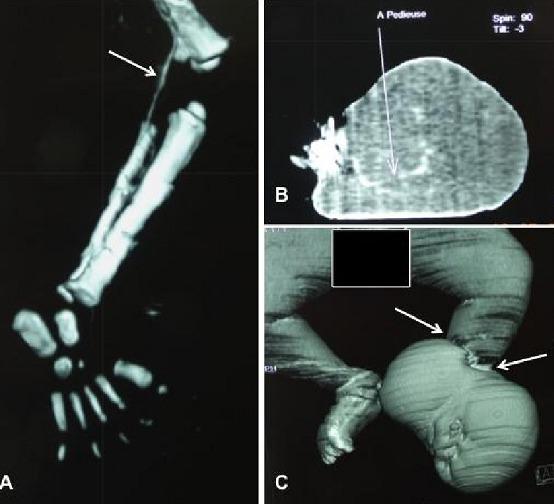

Amniotic band syndrome is a rare congenital disorder. The authors report the first cases documented at Souro Sanou University Hospital in Bobo-Dioulasso (CHUSS) in 2 male new borns. The malformations found at birth, were worn only on limbs and were in the form of skin furrow necking with a major lymphedema downstream. In both cases, the constriction furrow at member pelvic was associated with a club foot and a pseudosyndactyly in one case. Surgical treatment consisted of a section of the constrictor ring and a Z-plasty. The functional outcome was satisfactory with the acquisition of a plantar support for both children. Through these two observations, epidemiological, diagnostic, and particularities of the management of this condition are discussed in the Burkina-Faso.

羊膜带综合征是一种罕见的先天性疾病。作者报告了在博博迪乌拉索的苏罗萨努大学医院(CHUSS)记录的首例病例,两名男婴患有该病。出生时发现的畸形仅出现在四肢,表现为皮肤沟缩窄,下游伴有严重淋巴水肿。在两例病例中,盆腔部位肢体的缩窄沟在其中一例中伴有马蹄内翻足和假性并指。手术治疗包括切除缩窄环和进行Z成形术。两名患儿均获得了足底支撑,功能结果令人满意。通过这两例观察,讨论了布基纳法索这种疾病的流行病学、诊断及治疗特点。